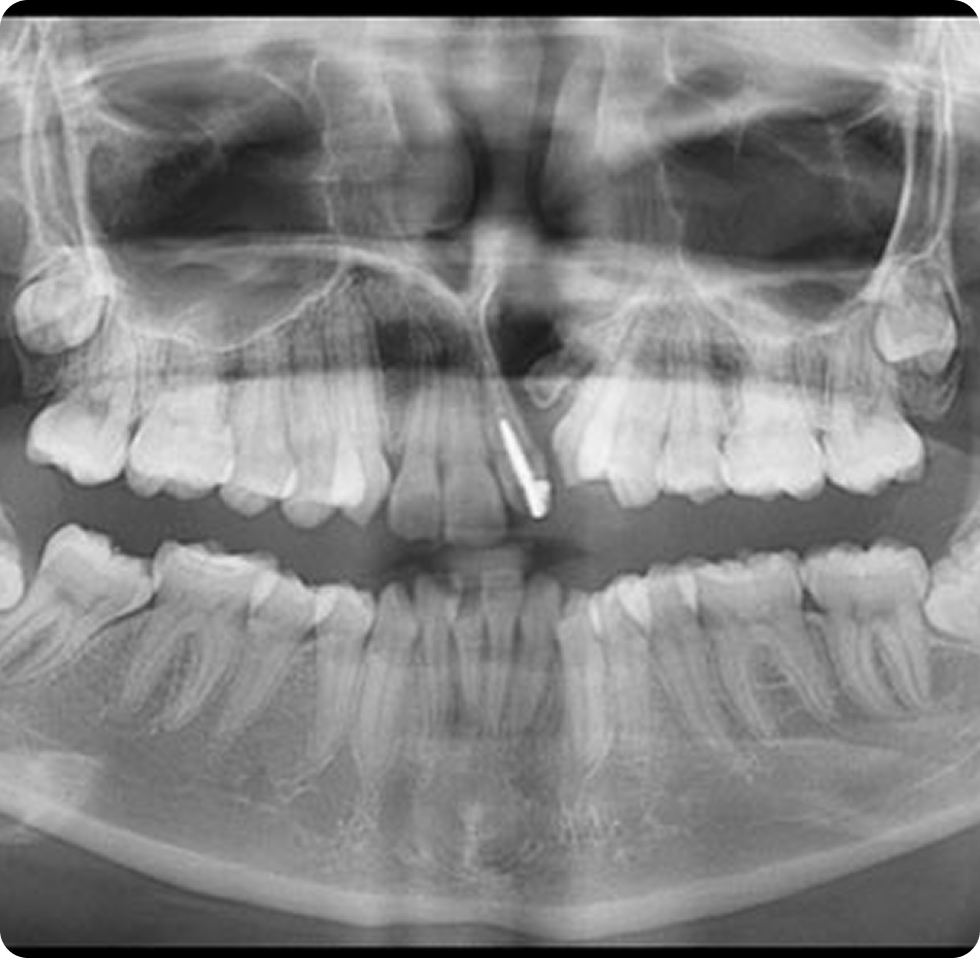

- Problemas dentales: El desarrollo dental puede verse afectado, con dientes que no se alinean correctamente o problemas en la erupción dental.

- Ortodoncia: A medida que los dientes de los niños crecen, puede ser necesario el uso de aparatos ortodónticos para corregir problemas de alineación y mordida.

- Ortodoncia: A medida que el niño crece, es probable que necesite aparatos ortodónticos para corregir problemas de alineación de los dientes y la mordida, ya que la fisura puede afectar el desarrollo dental.

- Tratamientos dentales: Algunos niños con paladar fisurado pueden tener dientes que no erupcionan correctamente o que están mal alineados debido a la fisura, lo que podría requerir restauraciones o intervenciones adicionales.